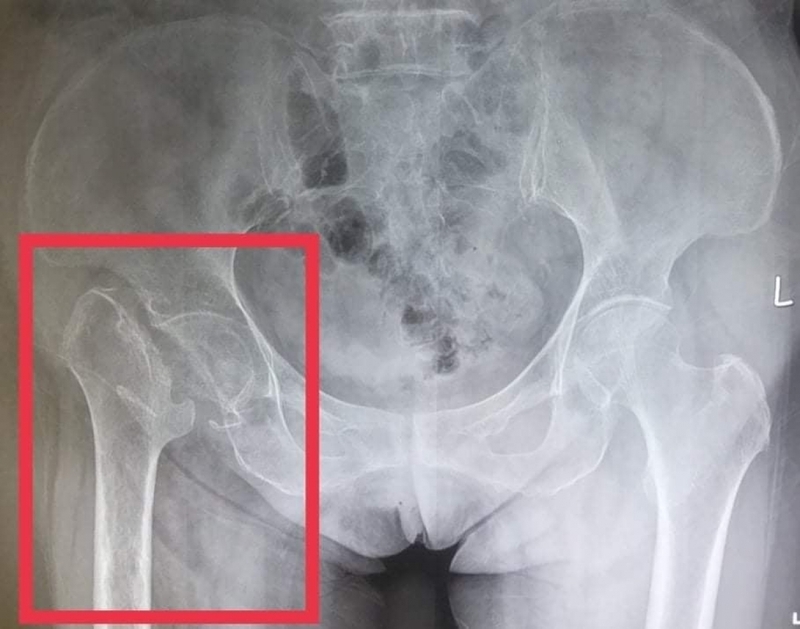

Gãy cổ xương đùi là tình trạng xương nằm ở vị trí giữa chỏm xương đùi và khối mấu chuyển xuất hiện dấu hiệu gãy, nứt, vỡ. Đây là hiện tượng rất phổ biến, đặc biệt xảy ra nhiều ở người cao tuổi.

Hình ảnh gãy cổ xương đùiTình trạng gãy cổ xương đùi là gãy xương nặng và ảnh hưởng rất nhiều đến sức khỏe của người bệnh vì khó điều trị dứt điểm, khả năng để lại di chứng nghiêm trọng khá cao. Cổ xương đùi có những đặc điểm như sau: